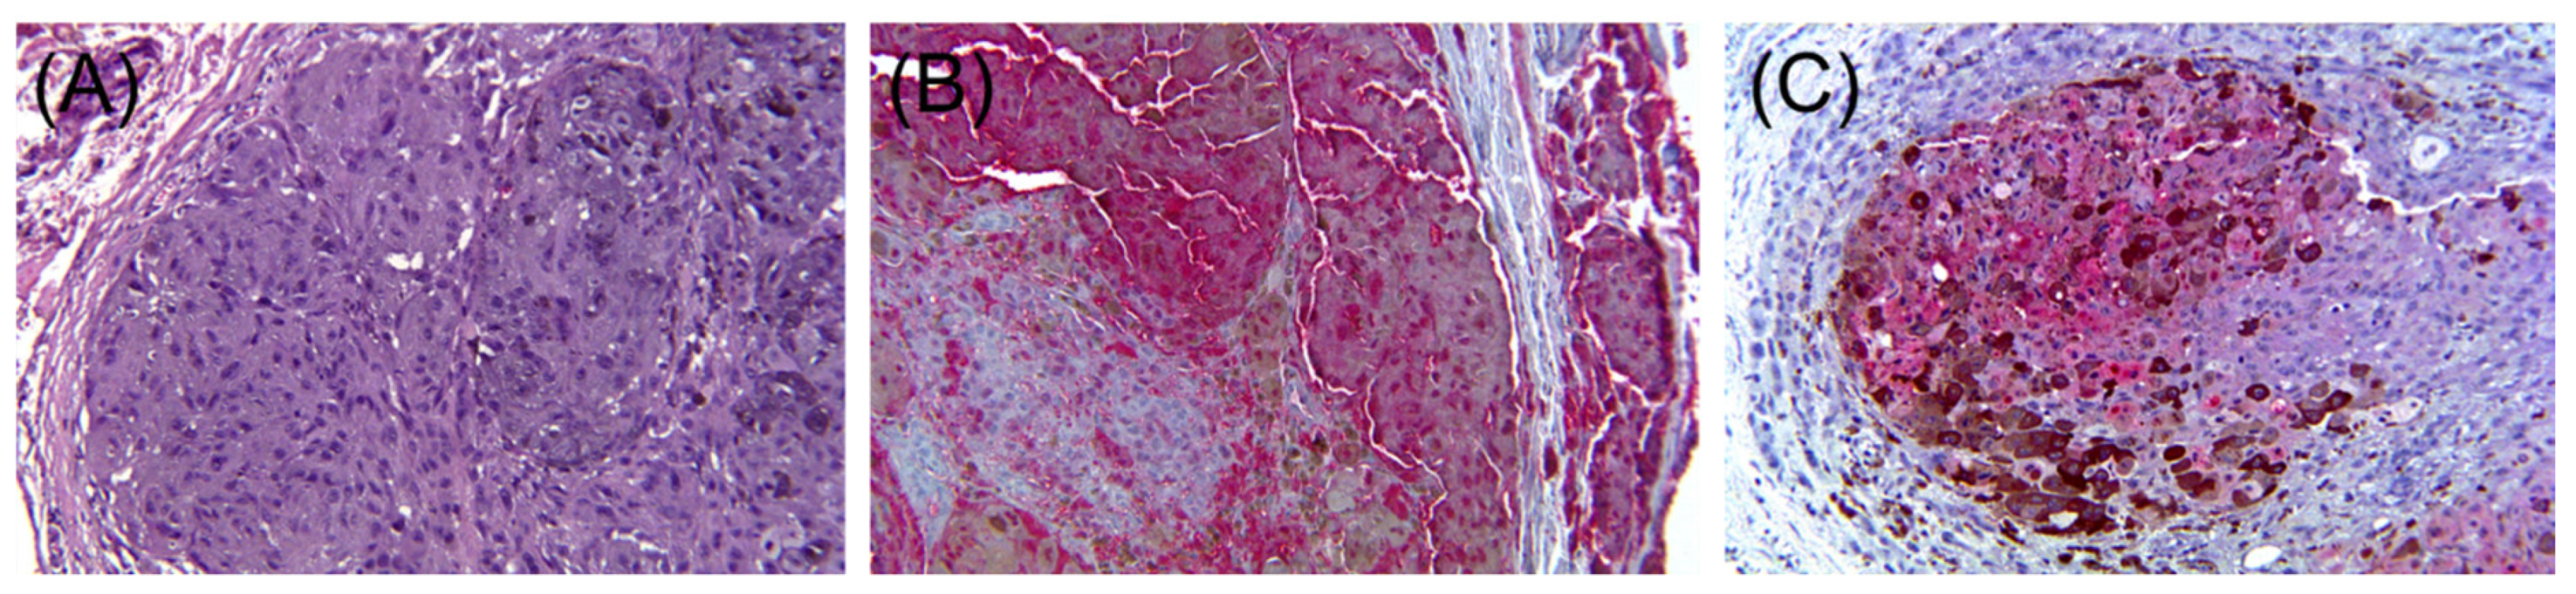

- Chang, O.; Argenyi, Z. Loss of Conventional Melanocytic Markers in Malignant Melanoma and Lymph Node Metastasis; an Uncommon but Dangerous Pitfall. Am. J. Dermatopathol. 2017, 39, 760–763. [Google Scholar] [CrossRef]